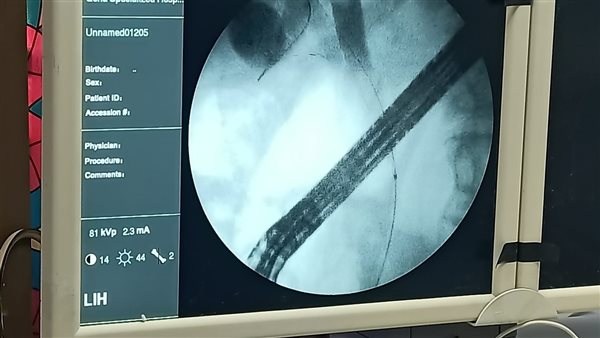

نجح فريق طبي بمستشفى الحميات والجهاز الهضمي والكبد بقنا، في إجراء عملية دقيقة ومعقدة باستخدام منظار القنوات المرارية لمريض يبلغ من العمر 56 عامًا، كان يعاني من ارتفاع حاد في نسبة الصفراء بالدم نتيجة انسداد مراري ناتج عن حصوات.

وأوضح الدكتور أحمد محمود صادق، وكيل وزارة الصحة بقنا، أن المستشفى استقبل المريض، وفور دخوله تم إجراء كافة التحاليل الطبية والإشاعات اللازمة التي أثبتت وجود حصوات أدت إلى انسداد كامل بالقنوات المرارية، مما استدعى إيداعه بالقسم الداخلي وتجهيزه بشكل عاجل لعمل منظار جراحي.

وتابع صادق، أن الفريق الطبي تمكن من استخراج الحصوات بنجاح تام وإجراء توسيع دقيق للقنوات المرارية لاستعادة وظائفها الطبيعية، مع تركيب دعامة مرارية لضمان تدفق الصفراء ومنع حدوث أي انسداد مستقبلي تأمينًا لحالة المريض الصحية.